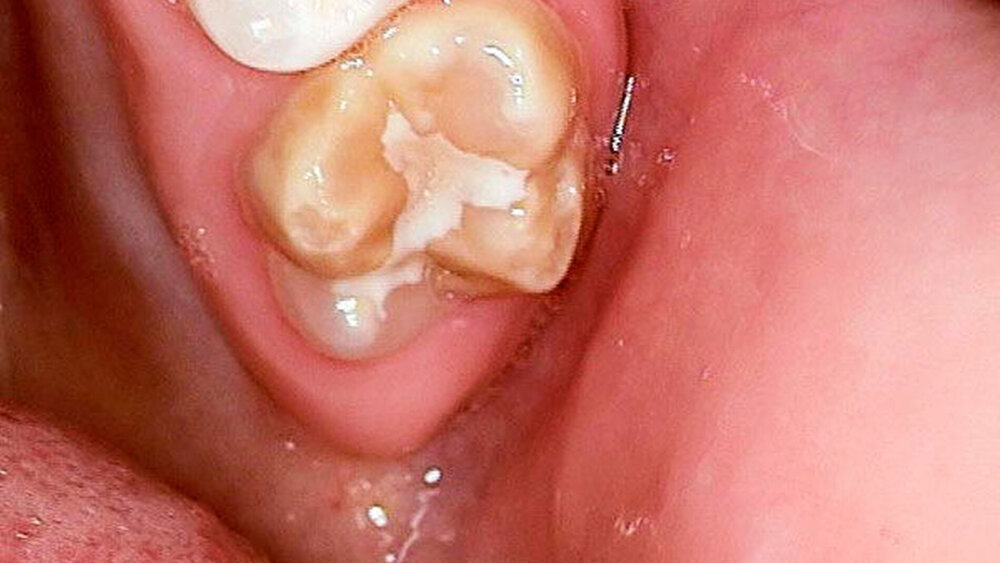

Ausgangsbefund:Während der extraorale Befund unauffällig war, zeigte der intraorale Befund ein kariöses Milchgebiss (Abbildungen 1 und 2).

Zweiter Befund nach drei Jahren:Im April 2011 stellte sich der Patient erneut im ZFZ vor. Mittlerweile war der Patient sieben Jahre alt und im beginnenden Wechselgebiss zeigten sich Schmelzhypoplasien der Sechsjahresmolaren (Abbildungen 3 bis 5). Da die Zähne starke Empfindlichkeiten und zunehmende Substanzverluste trotz versuchter Fissurenversiegelungen aufwiesen, hat der Hauszahnarzt mit den Eltern entschieden, diese weiter versorgen zu lassen. Somit wurde der Patient wieder ans ZFZ überwiesen zur erneuten ITN-Behandlung.